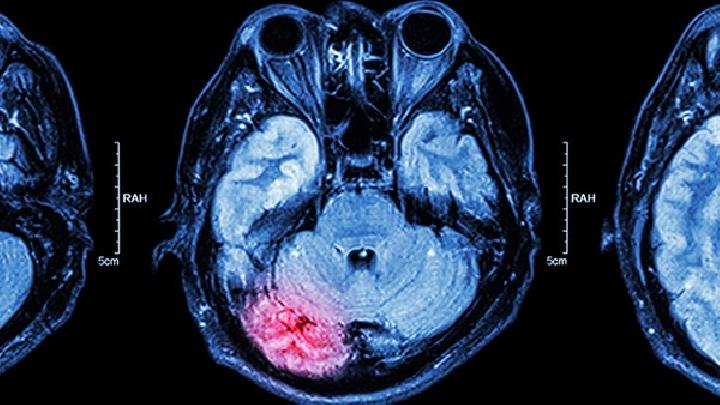

(4)占位性脑积水

占位性脑积水是指由颅内占位性病变引起的脑脊液分泌过多或循环障碍引起的脑积水。

一般来说,脉络丛乳头状瘤刺激脉络丛,使脑脊液分泌过多,导致占位性交通脑积水。其他颅内占位性病变多导致脑脊液循环梗阻和占位性梗阻性脑积水。